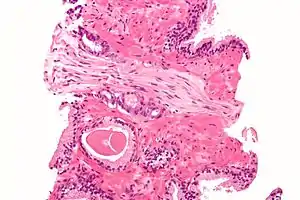

A diagnosis of prostate cancer requires a biopsy of the prostate be taken and examined under a microscope by a pathologist. Prostate biopsies are typically taken by a needle passing through the rectum or perineum, guided by transrectal ultrasound imaging, magnetic resonance imaging (MRI), or a combination of the two.[22][20] Ten to twelve samples are taken from several regions of the prostate to improve the chances of finding any tumors.[20] Biopsies are examined under a microscope by a pathologist, who determines the type and extent of cancerous cells present. Cancers are first classified based on their appearance under a microscope. Over 95% of prostate cancers are classified as adenocarcinomas (resembling gland tissue), with the rest largely squamous-cell carcinoma (resembling squamous cells, a type of epithelial cell) and transitional cell carcinoma (resembling transitional cells).[23]

Next tumor samples are graded based on how much the tumor tissue differs from normal prostate tissue; the more different the tumor appears, the faster the tumor is likely to grow. The Gleason grading system is commonly used, where the pathologist assigns a number from 1 (similar to prostate tissue) to 5 (least similar) for the most common pattern observed under the microscope, then does the same for the second-most common pattern. The sum of these two numbers is the Gleason score.[23] The total scores of 2 through 5 are no longer commonly used in practice, making the lowest score 6, and the highest score 10. Scores are commonly grouped into Gleason grade groups: a score of 6 or lower is Gleason grade group 1; a score of 7 with the first number (from the most common pattern) 3 and the second number 4 is grade group 2; the reverse – first number 4, second number 3 – is grade group 3; a score of 8 is grade group 4; a score of 9 or 10 is grade group 5.[23] Higher Gleason scores and higher grade groups represent cancer cases likely to be more aggressive with worse prognosis.[23]